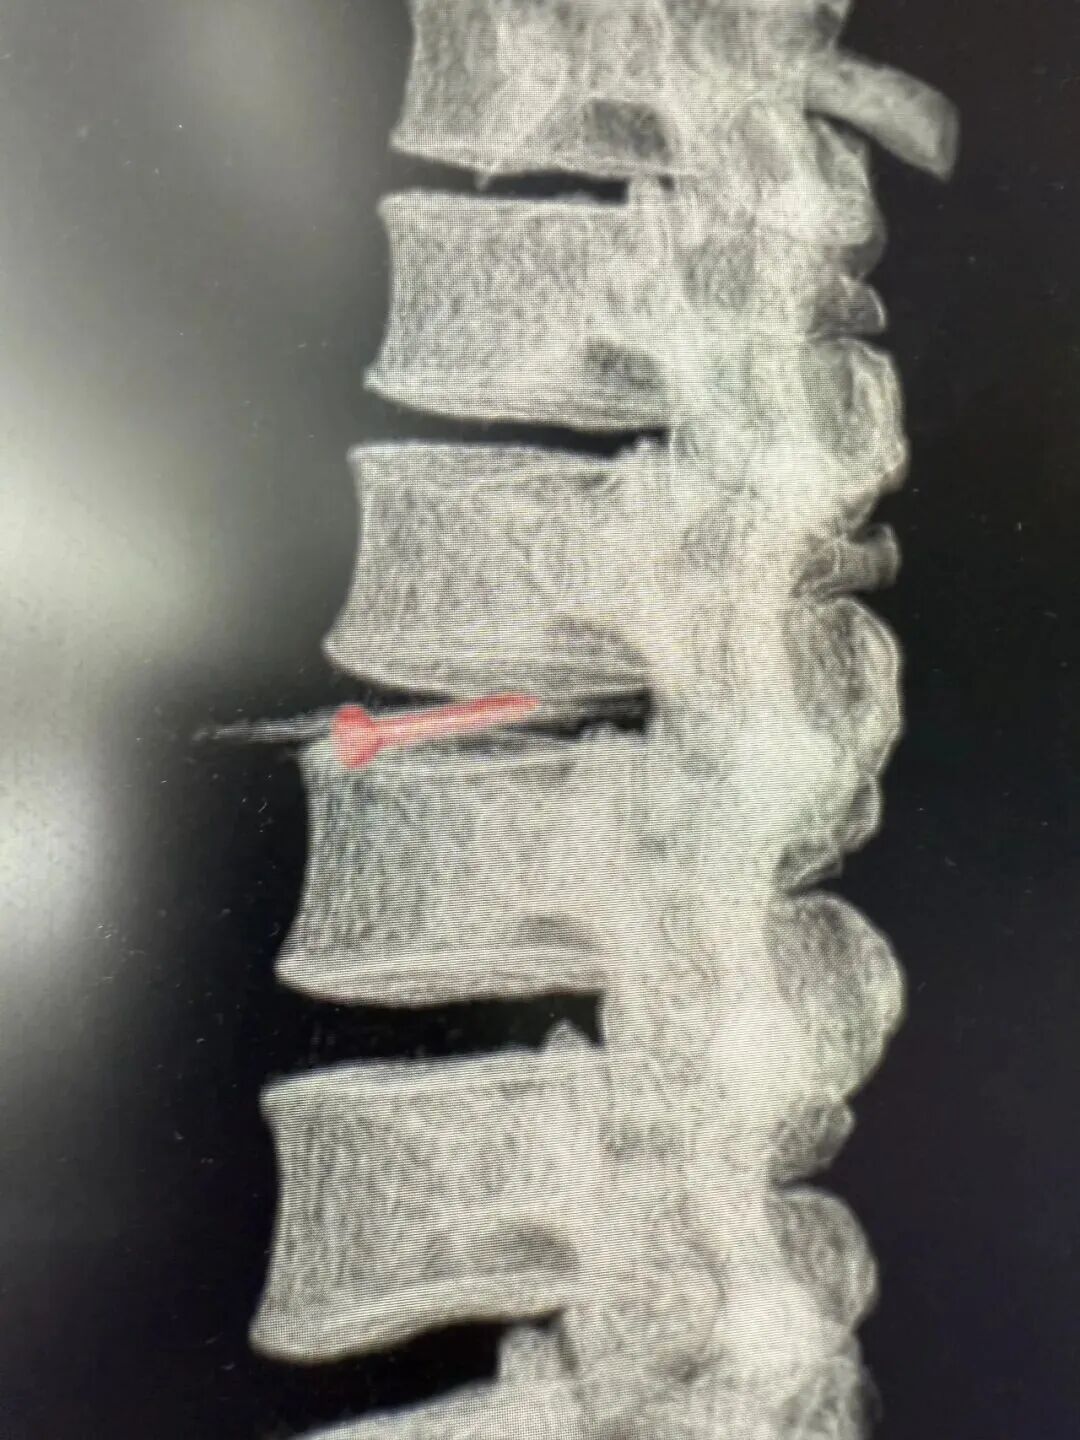

CT影像检查显示,

其腰椎间盘里卡着一枚

长约3cm的金属钉!

这根钉子从腹壁到椎间盘,

“游走”了约40cm,

疑似穿了多个腹腔脏器!

医生称,此枚金属钉依次刺穿腹壁、肝脏左叶、胃壁、结肠系膜、十二指肠、后腹膜,最终嵌插于腰椎间盘内,若处理不好很可能术后出现胆瘘、肠瘘等问题。经过3小时的手术,张师傅体内的钉子终于被取出,且取出后确认是一枚尾部有火药的工程钉

医生表示,虽然刺穿多个脏器,不过幸运的是,钉子穿过腹部时,并未伤及各大血管,并且正好钉在椎间盘之间,未伤及脊髓